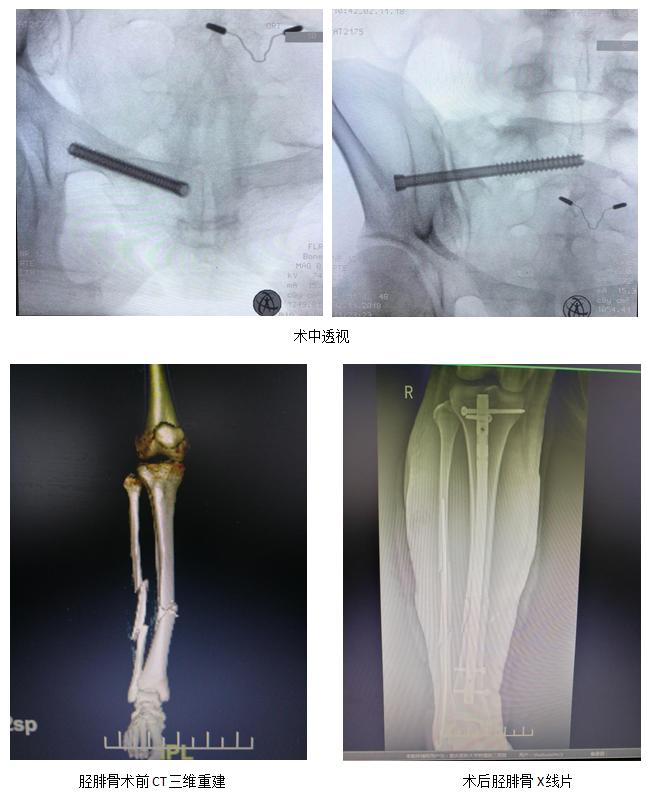

随着麻醉的起效,患者全身多处骨折闭合复位内固定手术顺利进展,凭着扎实的临床经验,主刀医生郑明顺利置入骨盆后侧的骶髂螺钉及前侧的耻骨支通道螺钉。在助手牵拉、旋转、复位的密切配合下,精准的将患者的多段腓骨粉碎性骨折闭合复位成功!接下来的胫骨髓内钉闭合复位内固定也成功开展。

手术用时约90分钟,便完成了骨盆骨折、胫骨粉碎的骨折、腓骨粉碎性骨折一系列手术,患者出血仅约50ml,减少了患者出血、感染、神经损伤的风险。这对于羸弱的患者而言,无异于福音。并且,由于腓骨使用斯氏针作为内固定装置,节约了接近2万的费用,这对于患者目前的遭遇无异于雪中送炭........。